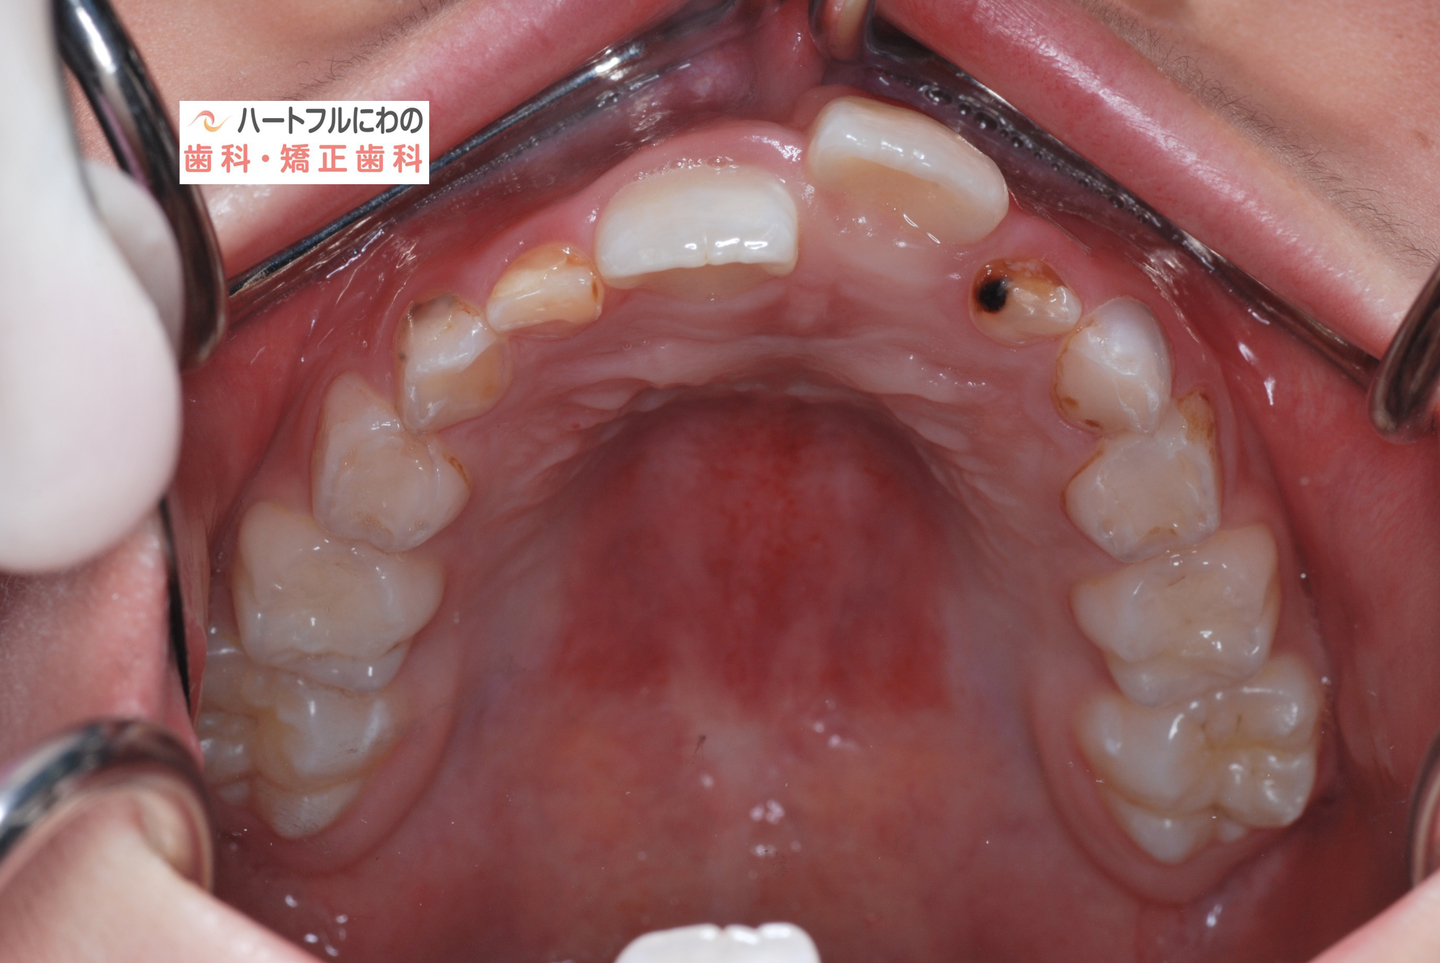

お口の中を拝見すると、上下の叢生(いわゆるガタガタ、乱ぐい)がみられ、多数の虫歯と歯肉炎がみられました。上唇小帯(上唇のすじ)の問題もありました。口呼吸で口腔内が乾燥すると通常の何倍も歯垢が付きやすくなり、虫歯や歯肉炎が頻発します。口呼吸の強い子は重なっている部分のかみ合わせが深い(下の歯がほとんどみえない)のもよく見られる特徴です。

その間に食事指導も含め、虫歯や歯周炎の管理も行います。このお子さんは炭酸を含む清涼飲料水が好物でその指導に苦労しましたが、初診時以降は虫歯の発症なく、思春期性の歯肉炎も軽度ですんでいます。